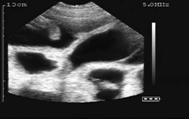

23 days of gestation

24 days of gestation

25 days of gestation